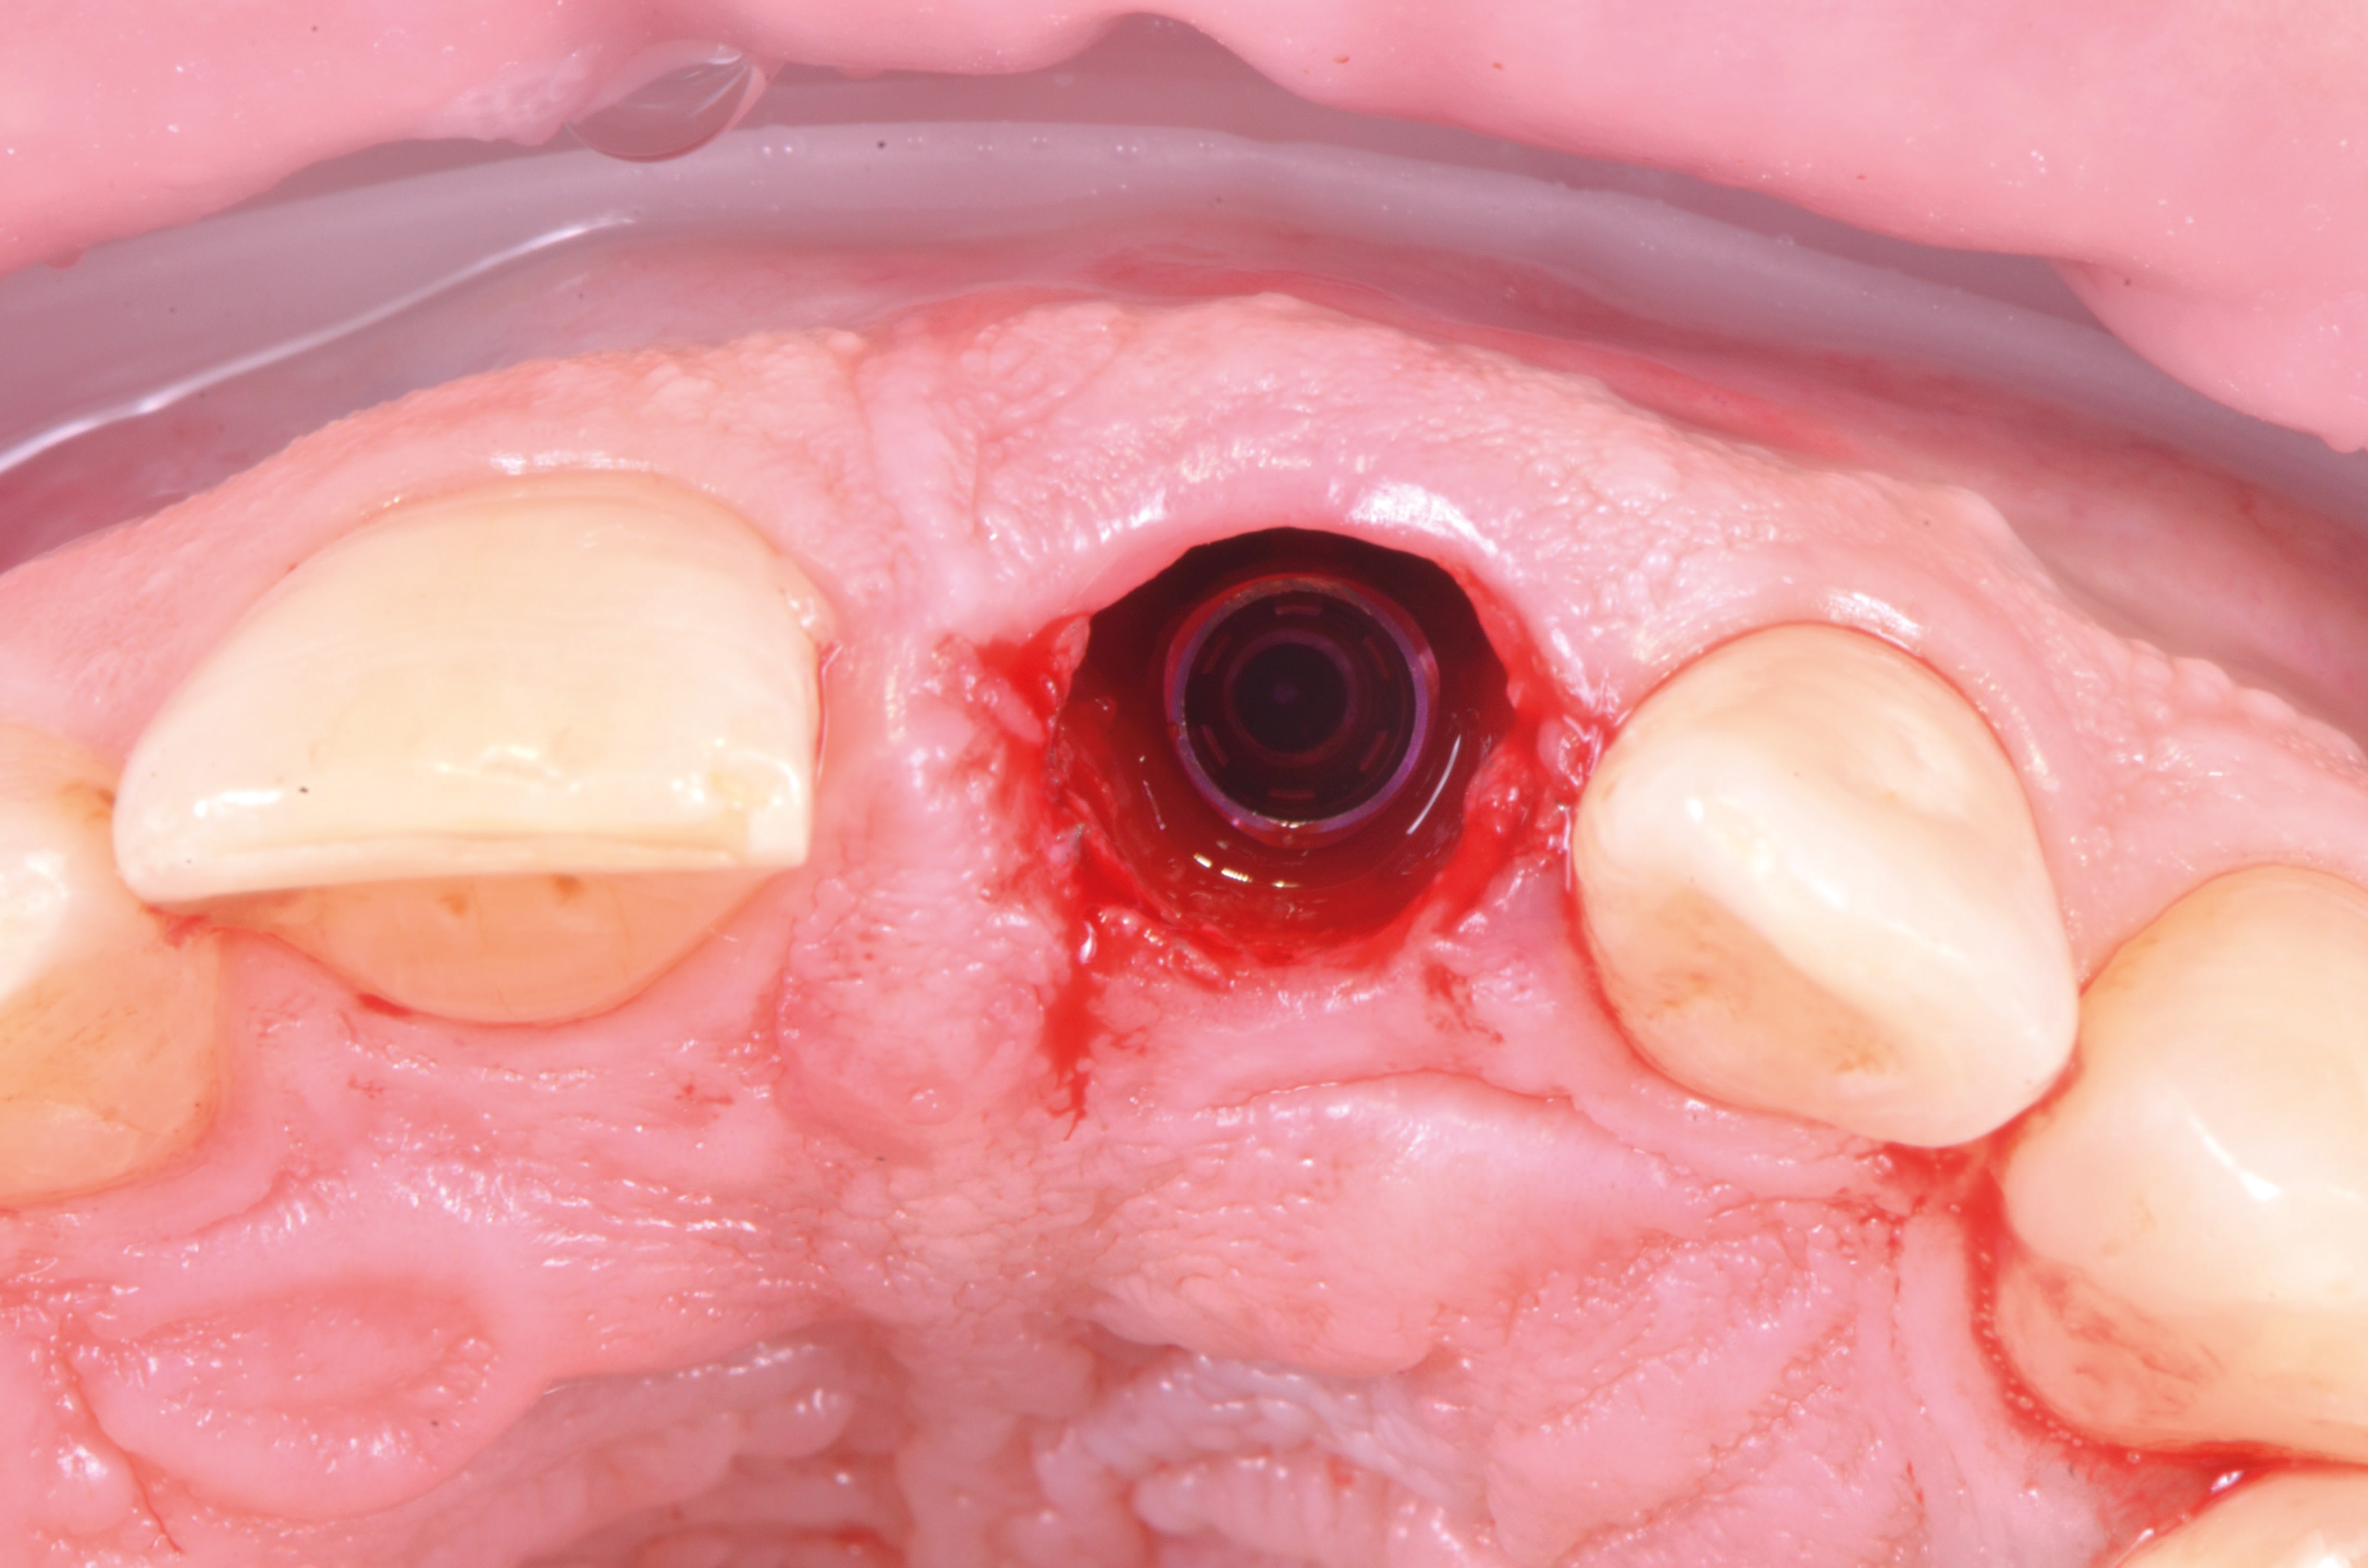

Una volta posizionata la dima chirurgica si è eseguita l’osteotomia guidata con frese a diametro crescente ed è stato posizionato l’impianto (MIS V3, MIS Implants ltd global, Bar Lev, Israele)(fig.7,8).

Seguendo le indicazioni del progetto chirurgico/protesico è stato posizionato un pilastro intermedio in titanio anodizzato (MIS Connect, MIS Implants ltd global, Bar Lev, Israele) con la tecnica del “one-abutment-one-time” con lo scopo di spiazzare la connessione protesica in una posizione più coronale (fig.9).